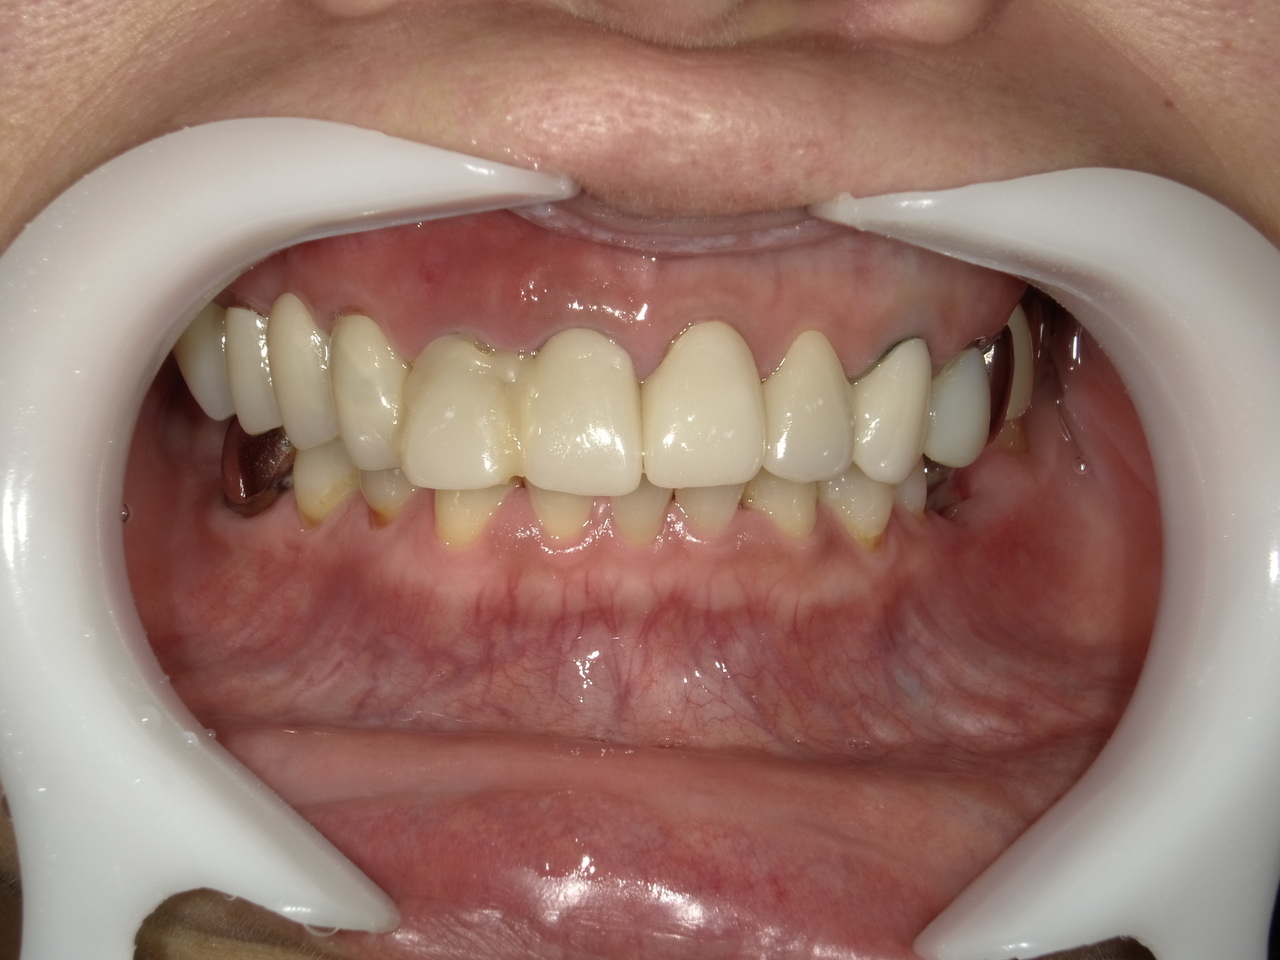

3.左上5の頬・舌側の大幅な骨欠損と上顎既存骨3mmまでの骨欠損がおこった症例に対しておこなったインプラント治療

Before

枚方市のインプラントの症例

After

I・K 様 女性 40代

症状としては、左上5の歯根破折を起こしていたため、排膿と自発痛をみとめた。それにともなう骨の大きな欠損。

治療法としては、炎症が強くたったためと、炎症による頬側側歯肉の退縮を認めていたために、まず、抜歯を行い上顎洞内及び歯抜した周囲組織の回復を試みた。その後、患者様がインプラント治療を希望したため、薄い上顎骨に対しては、グラフトレスサイナスリフト、骨欠損部には、人口骨補填を行い、頬側歯肉が退縮していることを改善するために、1回法でリーリングアバットメントを装着して、アバットメントの上に歯肉が覆うようにして、歯肉のボリューム回復を行った。2か月後、インプラントが骨と結合していることを確認して、光学印象を行い、2週間後にアバットメントとジルコニアクラウンを装着した。

治療結果としては、大幅な骨欠損があったが、グラフトレスサイナスリフトと骨欠損部に人工骨を補填して、抜歯した穴が自然に治る状態にしたことで、2か月半という短い期間での治療を完了することができた。(仮に、GBRや通常のサイナスリフトでの治療を行っていたら、最低でも1年は、かかってくる治療であると考える。)また、今回は、即時荷重を避け、1回法での治療を行ったことで、噛めない期間ができてしまったが、1回法で行ったことにより、歯肉のボリュームが増して、ブラッシングがしやすい口腔内環境にすることができた。低侵襲で、短時間で、治療を終えることができ、また、審美性・機能性の回復も行えたことができた。

治療の期間・回数:約2.5か月、6回

治療の価格:368,500円(税込)

治療費の内訳:インプラント基本料(フィックスチャー及び手術費用、投薬費用、レントゲン費用、インプラント上部費用(アバットメントおよびジルコニアクラウンの費用用)330000円(税込み)。オプション費用グラフトレスサイナスリフト費用プラス人工骨費用 38500円(税込み

治療のリスクや副作用:手術後に、痛みや腫れ、出血、合併症などを引き起こす可能性があります。噛む感覚がご自身の歯と異なる場合があります。見た目がご自身の歯と異なる場合があります。手術後にメインテナンスを継続しないと、インプラントが抜け落ちる可能性があります。